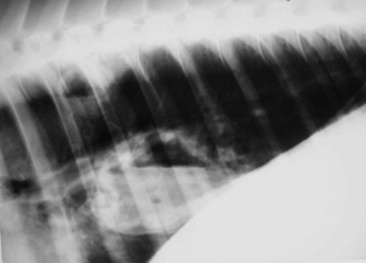

Radiography

Radiographs are indicated when the clinician suspects a congenital anomaly involving any thoracic structure; infectious disease of the pleura, pulmonary parenchyma, racheobronchial tree, or mediastinum; pneumothorax or pneumomediastinum; thoracic neoplasia of any origin; or trauma. Radiographs are frequently coupled with thoracic ultrasonographic evaluation. If significant accumulation of pleural fluid is suspected based on physical examination findings, the ultrasonographic portion of the examination should be performed first and radiographs obtained after drainage of excess fluid, as fluid may obscure potentially important parenchymal disease. The equipment needed to perform radiographic evaluation of the upper airway is available in most private practices, and most large referral and university practices have the equipment needed to perform thoracic radiography in larger patients such as adult horses and cattle. Digital radiography is becoming more commonplace and may replace more convention radiography in many practices and referral clinics over the next few years. Because of its configuration, the thorax in adult horses and cattle is filmed in the standing lateral position, generally requiring a series of three or four separate but overlapping images; thus the benefit of the ventrodorsal view in which the two lungs may be compared is lost. Neonates and small ruminants can be more readily handled and retained in recumbent positions, allowing for multiple recumbent views.

Page 493

Skull and cervical radiographs offer diagnostic information for evaluation of the upper respiratory tract. For large animal species, standing lateral skull films are easily obtained, and, with practice and adequate sedation, ventrodorsal and oblique projections can also be obtained in most patients. Certain difficult patients may require general anesthesia in order to obtain radiographs of diagnostic quality. In these cases other imaging modalities such as computed tomography (CT) and magnetic resonance imaging (MRI) might also be considered if available. Skull radiographs image the sinuses, pharynx, and larynx, allowing for assessment of anatomic dimensions of the pharyngeal and laryngeal structures. Sinuses affected by neoplasia or inflammation may show abnormal tissue density, a horizontal fluid line on a standing lateral film, bone lysis around the affected sinus, or alveolar periostitis. Thorough evaluation of the sinuses and nasal passages requires lateral, dorsoventral, and oblique views. Foreign bodies can be assessed in many cases. The equine guttural pouches are evident on lateral skull projection, and abnormal fluid accumulation, distortion by enlarged retropharyngeal lymph nodes, or emphysema can be radiographically apparent.

Radiographic assessment of the thorax of large animals remains preferable to ultrasonographic examination for detection of diffuse parenchymal diseases such as interstitial pneumonia, pulmonary edema, equine multinodular pulmonary fibrosis (EMPF), fungal pneumonia, acute lung injury (ALI), acute respiratory distress syndrome (ARDS), chronic disorders, and deep parenchymal or mediastinal abscesses. Unfortunately, many radiographic changes in equine respiratory disorders tend to be nonspecific or, in certain disease such as EIPH, inflammatory airway disease (IAD), or heaves, minimal to nonexistent.

Four types of radiographic patterns are described for the thorax: alveolar (airspace), interstitial, bronchiolar, and vascular. Opaque areas coalesce and fully obliterate vessels and bronchi in the alveolar pattern; air bronchograms may be prominent. This pattern is common in pulmonary edema, pulmonary hemorrhage, EMPF, ALI, ARDS, lung consolidation, and neoplasia. Interstitial patterns are the most common patterns noted in equine thoracic radiographs and are characterized by a blurring of the edges of pulmonary vessels, a diffuse increase in lung density, and variable reticular, linear, and nodular opacities. The reticular pattern is most commonly associated with more diffuse infectious lung diseases, pulmonary edema, interstitial pneumonia, and pulmonary fibrosis, whereas the irregular linear pattern is seen most commonly with resolving bronchopneumonia. A nodular pattern is seen with abscesses, granulomata, and neoplasms. It is rare to see a pure bronchial pattern in a horse, and it usually seen in association with an interstitial pattern. An exception is paired linear opacities or numerous small circular opacities (donuts) representing thickening of large or medium airways in equine bronchitis and bronchiolitis. The vascular pattern is seen in horses radiographed immediately postexercise or in animals with left-to-right cardiac shunts. Finally, extraparenchymal problems such as pleural effusions or free gas may be seen on thoracic radiographs of large animals. Thoracic radiology may be used for evaluation of potential rib fracture but is far less sensitive than thoracic ultrasonography in this regard.